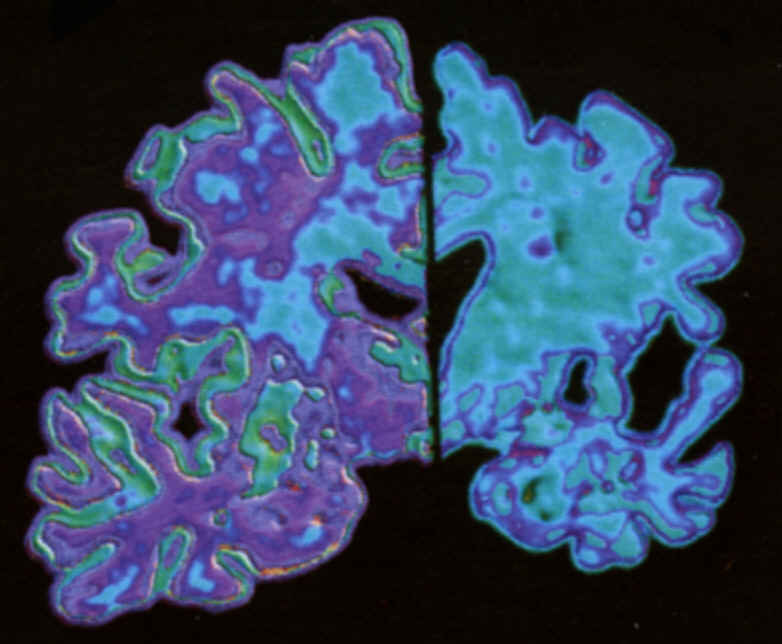

Alzheimer: la massa cerebrale regredisce ogni anno del 2,8 percento

Ogni anno chi sta per sviluppare la demenza di Alzheimer perde il 2,8% del volume del cervello. E’ quanto e’ emerso da una tavola rotonda dedicata a questa malattia organizzata da Atena Onlus, associazione di ricerca per le terapie neurochirurgiche avanzate. La misurazione della progressione della perdita di volume del cervello e’ stata descritta dal professor Paolo Maria Rossini, direttore scientifico dell’Associazione Fatebenefratelli per la ricerca.